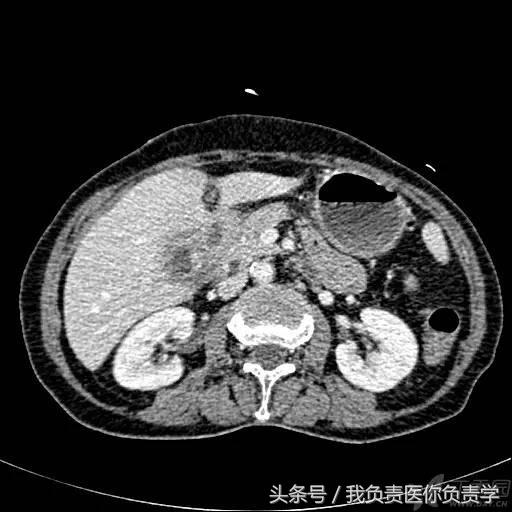

典型病例 5

患者女,75岁,右上腹疼痛就诊。查体示右上腹压痛明显,无明显腹膜炎体征。

超声检查发现胆囊内可见沉积物及结石回声,胆囊近底部可见 0.5cm 回声中断,十二指肠亦可见 0.5cm 回声中断,二者间见 5.8×4.4cm 混合性团块。

图1示胆囊饱满,内透声差,可见沉积物回声

图2示胆囊、胃窦及十二指肠之间可见混合回声型团块

图3-图5为胆囊局部放大图像,显示胆囊囊壁局部回声中断,周围可见不规则混合回声团块

图6和7为相应CT表现

术后诊断为慢性结石性胆囊炎,胆囊-十二指肠穿孔并内瘘形成。